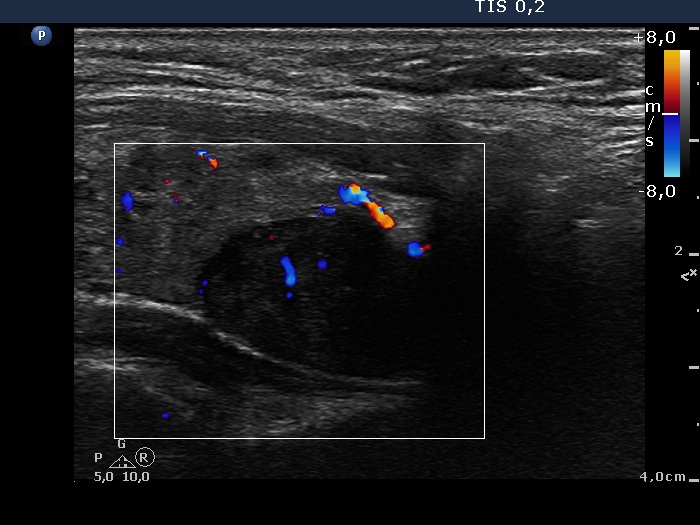

Ultrasonography: The thyroid was echonormal and contained multiple inhomogeneous, hyperechogenic nodules. There was a hypoechogenic lesion in the dorsal part or dorsal to the lower pole of the right lobe.

Aspiration cytology resulted in benign lesion which might correspond to parathyroid adenoma.

Wash-out thyroglobulin exceeded 476 mg/L wash-out parathormone exceeded 175 pg/mL.